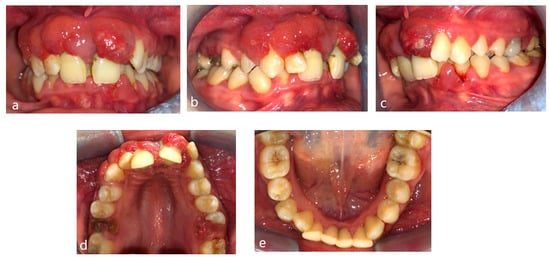

A 15-year-old female teenager was referred by a general practitioner to the Department of Periodontology, Faculty of Dental Medicine, University of Medicine and Pharmacy Carol Davila, Bucharest, Romania. There were no other diseases, such as diabetes or other hematological disease, no smoking, and no medications being taken by the patient. She had an accident (falling down the stairs) when she was 7 years old but did not experience any general or dental trauma (without notable objective or subjective clinical signs) as a result. Consequently, she did not visit a dentist for any treatment. The reasons for the first visit were teeth mobility, which appeared 2 years behind, poor aesthetic aspect of gingiva, and poor masticatory performance. The following clinical parameters were assessed at baseline: bleeding upon probing (BOP), plaque index score (O’Leary et al.) [12] and probing depth (PD). All measurements were performed by the same examiner using a periodontal probe (North Carolina 15 mm probe) on six sites for each tooth. The initial examination revealed deep probing pocket depth, severe gingival overgrowth, bleeding upon probing, and gum recession. Gingival inflammation was observed. Periodontal abscesses were registered to both maxillary central incisors (Figure 1). Suppuration and tooth mobility were registered to both maxillary central and lateral incisors. Gingival overgrowth was registered mainly on the maxillary anterior tooth side.

Figure 1.

Clinical aspects before periodontal treatment: (a) frontal aspect, (b) right lateral aspect, (c) left lateral aspect, (d) maxillary occlusal aspect, and (e) mandibular occlusal aspect.